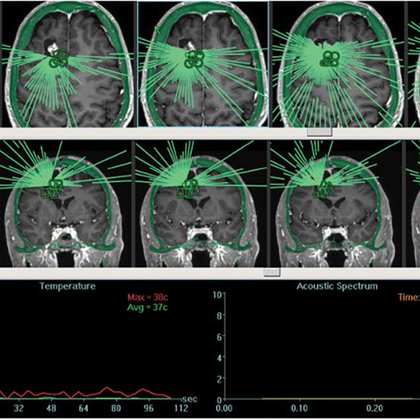

@ScienceTM

Science Translational Medicine

8 days

Sonodynamic therapy involving focused ultrasound and systemic 5-ALA is safe in patients with recurrent #glioma and shows preliminary signs of biological efficacy, according to a new pilot trial. @smehtalab @NaderSanai @IvyBrainTumCtr https://t.co/NH3jxnDQ34

So excited to get this paper out! Just in time for Thanksgiving. So very grateful to our patients and their families๐Ÿ™๐Ÿผ An early clinical trial of 5-ALA sonodynamic therapy in recurrent high-grade glioma | Science Translational Medicine https://t.co/hFCraWYzVz @IvyBrainTumCtr

Tweet card summary image

science.org

An early clinical study demonstrates feasibility of noninvasive 5-ALA sonodynamic treatment in nine patients with recurrent high-grade glioma.